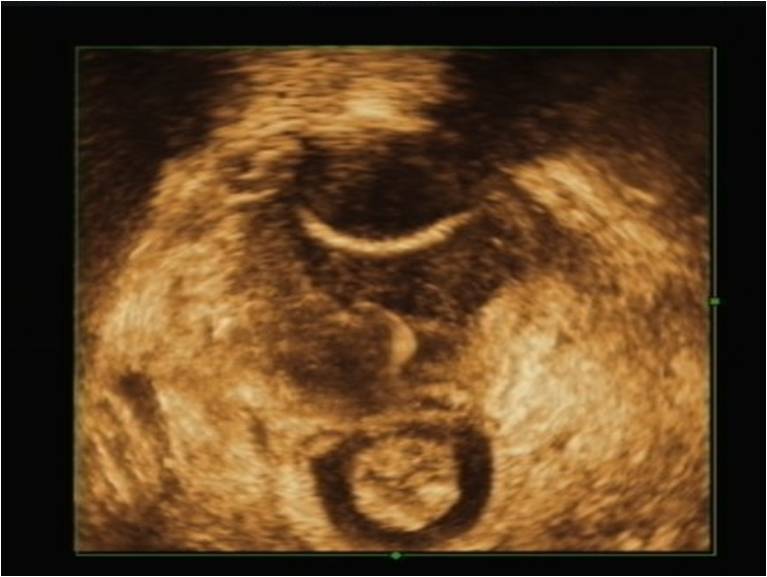

二维盆底超声主要是通过看到耻骨联合、尿道、膀胱、阴道、宫颈、直肠壶腹及肛管来评估盆底各脏器位置、功能,有无脱垂,在静息状态下测量残余尿量、逼尿肌厚度、尿道长度以及观察尿道括约肌形态,在静息及用力(Valsalva)状态下测量膀胱颈移动度,尿道旋转角度,膀胱后角角度,膀胱颈是否呈漏斗状,这些指标主要用于协助评估膀胱过度活动及压力性尿失禁,对于盆腔脏器脱垂患者在Valsalva动作时通过测量膀胱、宫颈、直肠壶腹与耻骨联合的距离来评估盆腔脏器脱垂程度。

经会阴二维盆底超声检查:S:耻骨联合,U:尿道,V:阴道,UT:子宫,A:肛管,R:直肠壶腹,L:肛提肌